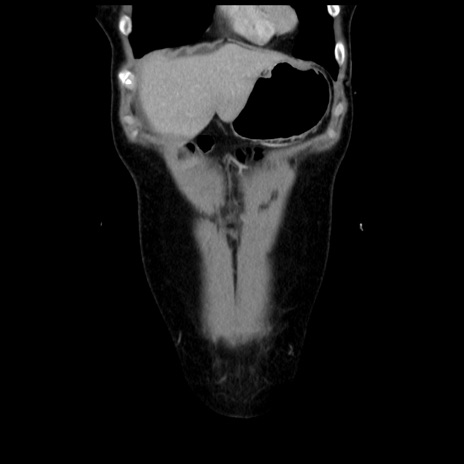

症例10(冠状断像)

【症例】 50歳代女性

【主訴】 腹痛

【現病歴】前日生レバーを食べた。今朝に排便あり。 昼前に突然発症の腹痛を生じ、当院救急外来を受診した。

【既往歴】 子宮筋腫にてで子宮全摘後

【身体所見】 意識清明、腹部:平坦、軟、下腹部やや左を中心に圧痛・反跳痛あり、筋性防御あり

【データ】WBC 7800、CRP 0.07